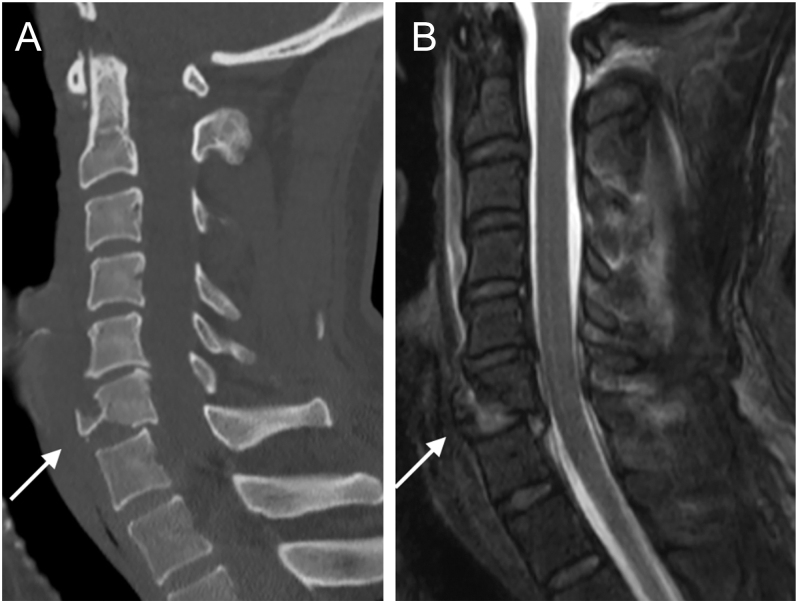

颈椎泪滴骨折的特征是位于椎体前下角的三角形碎片。屈曲型泪滴骨折是由屈曲-压缩机制引起的高度不稳定损伤。这些损伤的一个显著特征是椎体后滑脱,这通常与神经系统损伤的高风险相关。前路入路是屈曲型泪滴骨折最常用的手术治疗方法。相反,伸展型泪滴骨折主要影响椎体轴,通常是稳定的损伤,可以非手术治疗。

Teardrop fractures of the cervical spine are characterized by a triangular-shaped fragment located in the anteroinferior corner of the vertebral body. Flexion-type teardrop fractures are highly unstable injuries resulting from a flexion-compression mechanism. A notable feature of these injuries is retrolisthesis of the vertebral body, which is often associated with a high risk of neurological compromise. The anterior approach is the most commonly used surgical treatment for flexion-type teardrop fractures. In contrast, extension-type teardrop fractures primarily affect the axis vertebral body and are generally stable injuries that can be treated nonoperatively.